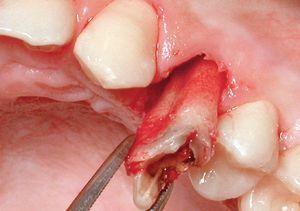

La extracción se efectuó usando las puntas del equipo de extracción (figura 1). La punta en forma de flecha se introdujo en el surco a una profundidad de 4-5 mm sin separar primero la encía del diente, alrededor de toda la circunferencia de éste. No se evidenció hemorragia mientras se progresaba en dirección apical (figuras 3a y 3b). Acto seguido, se usaron sindesmotomos rectos o angulados para cortar en profundidad las fibras del LPD (hasta 10 mm o más). Tras la sección de las fibras del ligamento, el diente se movilizó con un sindesmotomo de Claude Bernard (figura 3c) y se extrajo del alveolo con unas pinzas (figura 3d). En el caso de dientes anquilosados, se usaron sindesmotomos de vibración para desprender la raíz del hueso fijado circundante.

Figura 3 Procedimiento de extracción con las puntas vibratorias.

Figura 3c Para levantar el premolar se usó un elevador (sindesmotomo de Claude Bernard).

Figura 3d El diente se extrajo de una pieza con pinzas tras la elevación con un sindesmotomo manual.